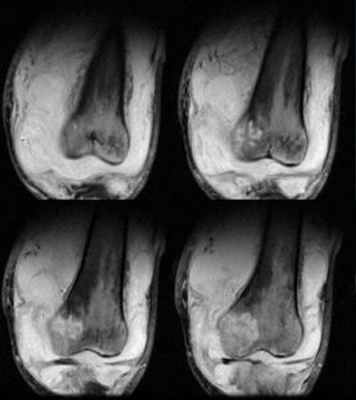

Кроме лабораторного выявления возбудителя, необходимо визуально оценить степень поражения опорно-двигательного аппарата патологическим процессом. При туберкулезе позвоночника МРТ позволяет определить уровень и тяжесть компрессии спинного мозга, выявить туберкулезный спондилит. Часто заболевание затрагивает суставы и МРТ является основным методом обследования благодаря возможности получения изображений в различных проекциях и высокой контрастности мягких тканей на снимках. Также магнитно-резонансная томография позволяет получать наиболее полную информацию о состоянии тканей на разных стадиях заболевания, что помогает при подборе индивидуальной схемы лечения. С помощью МРТ диагностируют туберкулезный артрит по характерным для него признакам — наличию очагов секвестрации, скоплению жидкости в полости сустава, пролиферации синовиальной оболочки. Томография уточняет локализацию и распространенность как костной деструкции, так и мягкотканных изменений, выявляет дегенеративные изменения связочного аппарата, деструкцию суставного хряща. Также могут определяться субхондральные и внутриэпифизарные кисты с жидким содержимым, специфичные для туберкулезного поражения. При экссудативных формах заболевания могут выявляться интра- и периартикулярные абсцессы.